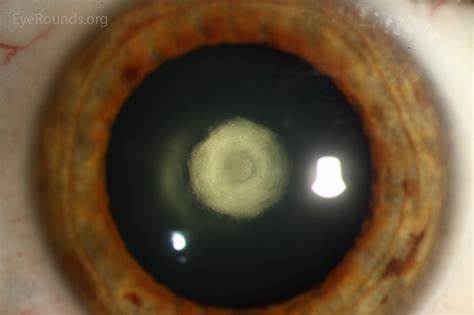

CATARACT SERVICES

CATARACT SURGERY IN HIGH RISK CASES LIKE POSTERIOR POLAR, HYPERMATURE CATARACT, WEAKER ZONULES, NON-DILATING PUPIL, POST UVEITIS CATARACT, POST RETINA SURGERY CATARACT, CATARACT WITH CORNEAL OPACITY UNDER TOPICAL ANAESTHESIA